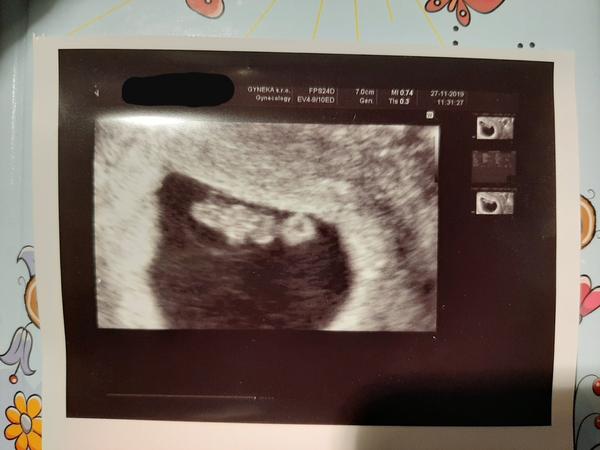

@donika ahoj, tak jsem tam dnes byla, a trochu se to zas posunulo... tak jsem 8tt 7+3 a TP 12.7.2020 miminko měří 7cm a 11.12. Už jdu do poradny a dostanu průkazku.

@zajusenka 7 centimetrů v 8 tt, to je asi omyl, ne? Jinak gratuluju a neboj, ono se to zlepší.

Asi se prepsala,spis kolem 1cm. Takze 7mm bude pravdepodobnejsi....7cm ma az kolem 13-14.tt

@vineta jj... omlouvám se za překlep 😅 7mm ... respektive na ultrauvuku je 7.4mm